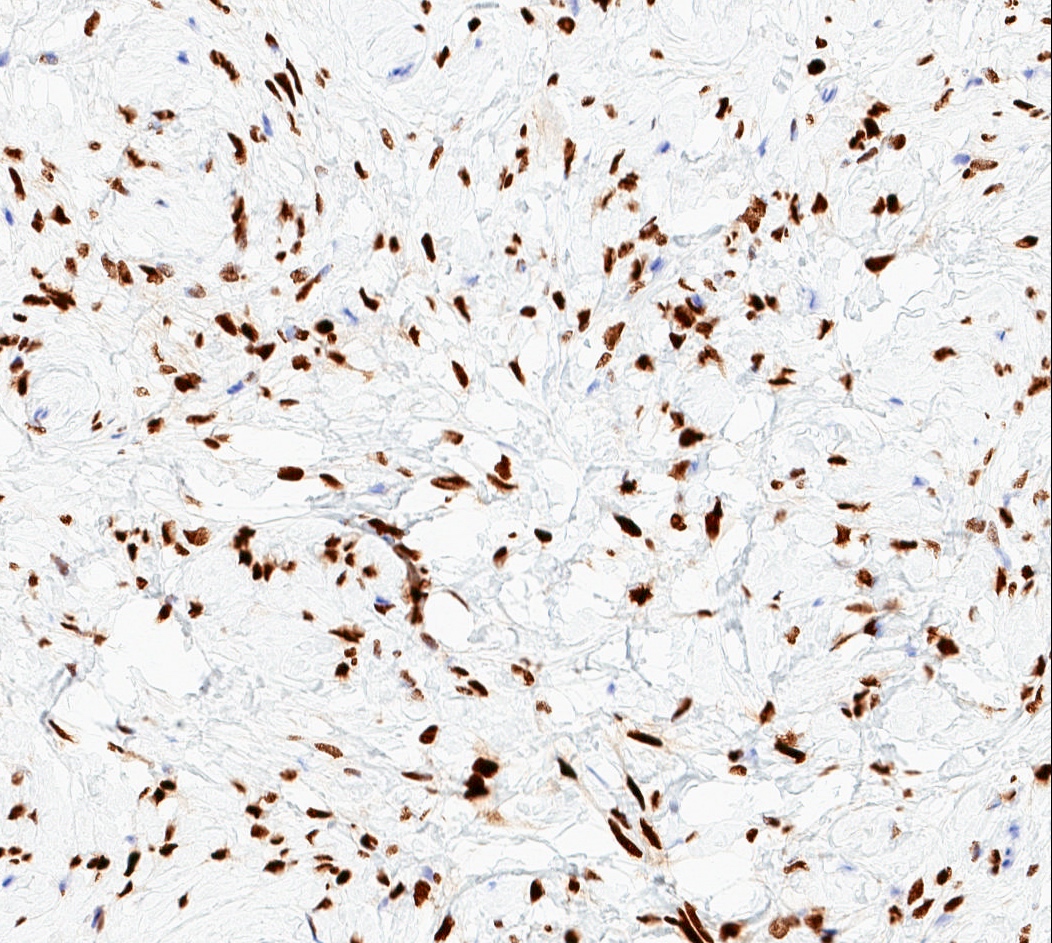

Microscopic (histologic) images

Positive stains

- Desmin (91%), vimentin, ER, PR, AR, BCL2, CD10, CD99 (Histopathology 2000;36:515, Virchows Arch 2007;450:727)

- CD34 (89%) diffuse and strong characteristic but may uncommonly show absent / focal expression (Am J Surg Pathol 2016;40:361, Breast J 2018;24:55)

- H-caldesmon if smooth muscle differentiation / leiomyomatous variant (Hum Pathol 2016;58:54, Histopathology 2003;42:233)

Negative stains

- Rb (negative in 89 - 92%) (Am J Surg Pathol 2016;40:361, Am J Surg Pathol 2012;36:1119)

- Actin (negative in 63%)

- Cytokeratins, S100, p63